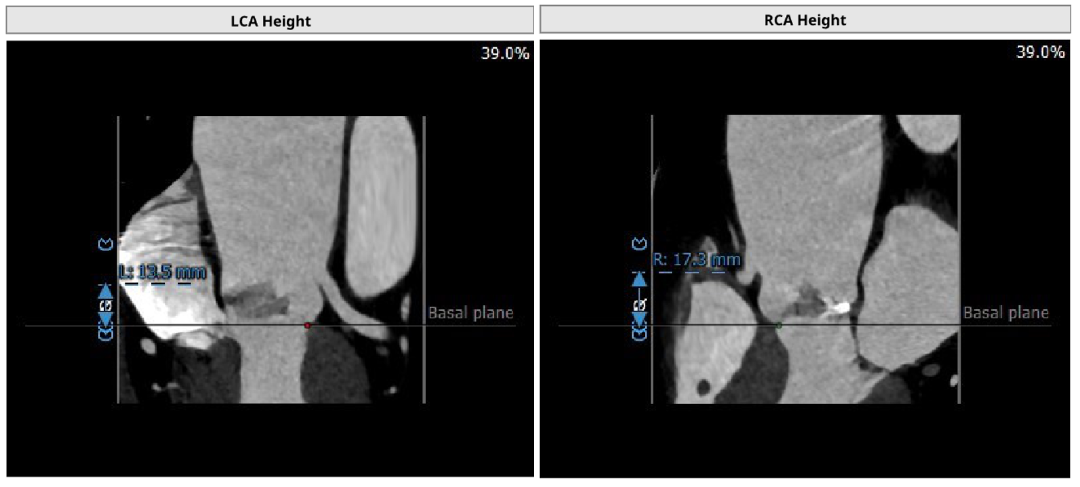

患者女性,73岁,Type 1二叶瓣,左-右融合。主动脉瓣重度狭窄,瓣环及瓣叶钙化,瓣环面积径24.9mm。左冠高度13.5mm,右冠高度16.8mm。外周入路可见明显钙化,内径尚可。

手术经心尖入路,术中植入25# RENATUS®球扩式经导管主动脉瓣。输送器顺利通过,瓣膜精准释放。瓣膜释放位置理想、形态及功能良好,术后无明显瓣中及瓣周反流等并发症。

张大发教授团队、李伟栋教授一致表示:RENATUS®的短瓣架设计对远期冠脉手术通路的影响小;每隔2mm的规格尺寸可精准匹配病人的不同解剖特点;经大组长期临床验证的有效抗钙化技术,能提供卓越耐久性;可扩张瓣架设计,优化未来瓣中瓣的治疗效果。

术前评估